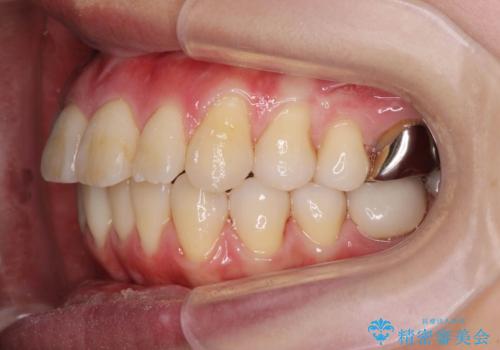

捻れた奥歯 突き出た前歯を治したい

- 出っ歯に見える前歯、捻れてしまった小臼歯の改善を求めて来院されました。

マウスピースでは改善の難しい小臼歯のねじれをまず部分ワイヤー矯正で改善し、その後マウスピース矯正で前歯の突出感を改善します。

時間はかかりましたが、捻れ、かみ合わせ、前歯の角度の改善が達成され満足いただくことができました。